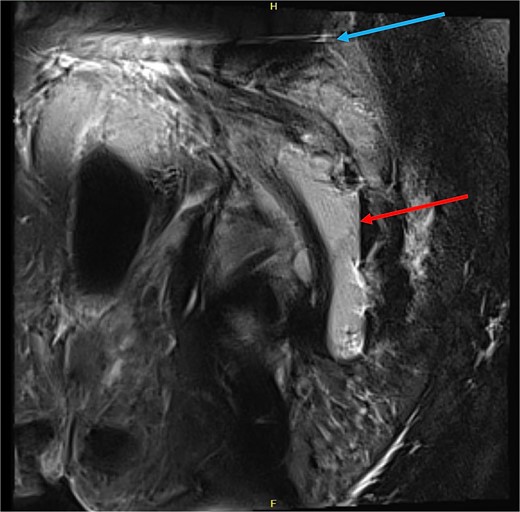

Despite repeat surgical debridement the patient failed to improve. He was managed in the intensive care unit due to septic shock and required a short period of vasopressor support. Pelvic computed tomography (CT) and magnetic resonance imaging (MRI) revealed a contiguous abscess extending from the surgical cavity through the greater sciatic notch and into the left gluteal region (Figs. 1 and 2). This extended toward the hip and abutted his sacral metalwork.

MRI pelvis (sagittal slice, patient lying lateral) demonstrating air-fluid level within the intermuscular abscess (red arrow), and artefact from SIJ screws (blue arrow).